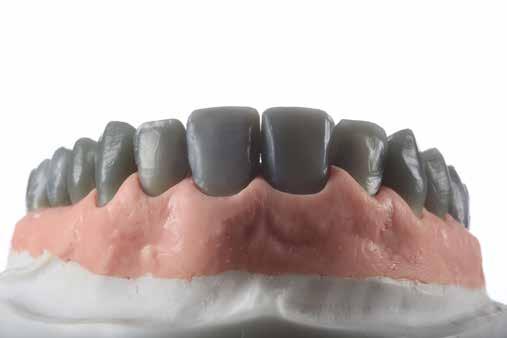

Mivel a rendelkezésünkre álló feszes íny szélessége lehetővé tette, ezért koronahosszabbítás helyett ínyplasztika végzése mellett döntöttünk. Először diagnosztikus gipszmintákat készítettünk, majd felviaszolás, azaz a wax-up (Wax GEO Classic, Renfert, Hilzingen, Németország) segítségével meg-

Az ultravékony héjpreparálás menete. (A): Az előkészítés mélységének ellenőrzése átlátszó redukcióssablon segítségével. (B): Az eltávolított anyag vastagságának ellenőrzése gyúrható szilikonból készült sablon segítségével. (C): Az okkluzális irányú redukció szilikonsablonnal történő ellenőrzése.

terveztük a páciens igényeinek megfelelő harmonikus mosoly biztosításához szükséges fogformákat és az ínylefutást. A diagnosztikus wax-up szkennelését (D2000, 3Shape A/S, Koppenhága, Dánia) követően digitálisan megterveztük a sebészi sablont, és azt 3D nyomtató segítségével (Form 3, FormLabs) rezinből (Dental LT Clear Resin V2, Form 2, FormLabs, Somerville, Massachusetts, Egyesült Államok) elkészítettük (4. ábra). A sebészi sablon fogakra történő helyezését követően egyértelműen látszott, mely vonalban kell az

Ezt követően 6 hónapot vártunk a parodontális szövetek gyógyulásának érdekében. Ekkor a mock-up-ot felhelyeztük a páciens fogaira. Mivel a páciens elégedett volt a bemutatott látvánnyal, ezért a kezelés következő fázisának megkezdése mellett döntöttünk. A preparálás előtt a fogak felszínén mélységjelölő barázdákat alakítottunk ki (LVS1 FG Medium Depth Cutting Diamond 834.31.021, Brasseler Dental, One Brasseler Boulevard Savannah, Georgia 31419, Egyesült Államok). A megfelelő anyagvastagság biztosításához ezen felül egy 0,5 mm vastagságú átlátszó redukciós sablont (Keystone Industries, 480 South Democrat Road, Gibbstown, New Jersey, Egyesült Államok) is készítettünk. A sablont egy vákuumkészülék (Pro-Vac Machine 110V, Keystone Industries) segítségével hoztuk létre. A protetikai fázis során a frontfogak és az első kisőrlőfogak kerámia héjakkal történő ellátását terveztük. A preparálás mélységét a sablon felhelyezését követően, a sablonon lévő perforációk segítségével tudtuk ellenőrizni. A nyílásokba parodontális szondát vezettünk, hogy meghatározzuk a redukció mértékét (6. ábra). A preparálás megfelelőségét ezen felül egy gyúrható szilikonból készült sablonnal is ellenőriztük. Ebben az esetben is parodontális szondát használtunk a mélység ellenőrzése céljából (6. ábra). A csonkelőkészítés utolsó lépéseként a lecsiszolt fogfelszíneket polírkorongok segítségével (OptiDisc, Kerr, Orange, Kalifornia, Egyesült Államok) simára políroztuk. A lenyomatvétel során duplafonalas lenyomatvételi technikát alkalmaztunk. Az ínybarázdákba először #00-

ás, majd #0-ás retrakciós fonalakat (Ultrapak, Ultradent Products Inc, South Jordan, Utah, Egyesült Államok) helyeztünk. A végső precíziós lenyomatot polivinil-sziloxán lenyomatanyaggal (Virtual 380, Ivoclar Vivadent AG, Schaan, Liechtenstein) vettük. A fogtechnikai fázisban ultravékony (0,5 mm-nél vékonyabb) földpátkerámia héjak elkészítését kértük (Super Porcelain Ex-3, Kuraray Noritake Dental, Tokió, Japán), (7. ábra). A kerámia héjak készre vitelét követően a próba során a héjakat a helyükre illesztettük a széli zárást, az így kialakított fogformák ellenőrzése céljából. A páciens elégedett volt az így kapott látvánnyal. A végleges ragasztás kofferdám izolálásban történt. A preparált fogak felületét először 37%-os foszforsavval (Total Etch, Ivoclar Vivadent) 15 másodpercen keresztül kondicionáltuk, majd vízzel leöblítettük (8. ábra). A kondicionált zománcfelszíneket Adhese Universal (Ivoclar Vivadent) adhezívvel kezeltük. A kerámiahéjak homorú felszíneit 5%-os folysavval (IPS Ceramic Etching Gel, Ivoclar Vivadent) 20 másodpercen át kondicionáltuk, majd a felszíneket Monobond Plus primerrel (Ivoclar Vivadent) vontuk be (7. és 8. ábrák). A héjakat fényre kötő rezinalapú ragasztócement (Variolink Esthetic LC, Ivoclar Vivadent) applikálását követően a helyükre illesztettük. A kifolyó cementfelesleg eltávolítását követően minden felszínt (labiális, palatinális, meziális és distális) LED-es polimerizációs lámpával (VALO Cordless, Ultradent) 40 másodpercen keresztül megvilágítottuk.